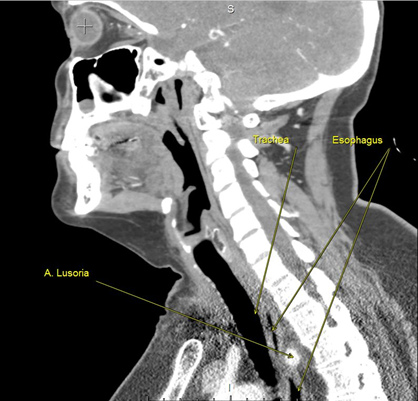

В послеоперационном периоде больная была дополнительно обследована: выполнена компьютерная томография шеи и органов грудной клетки с ангиографией (рис. 3 а, б) и прямая ангиография (рис. 4), по данным которых подтверждено наличие у пациентки аномалии развития ветвей аорты. Правая подключичная артерия отходит от уровня перешейка аорты по ее задней поверхности самостоятельным стволом, проходя между аортой и позвоночным столбом на уровне третьего позвонка, – a. lusoria. От правой подключичной артерии отходит правая позвоночная артерия. Правая общая сонная артерия отходила от аорты одним устьем вместе с левой общей сонной артерией, что наглядно демонстрируется на ангиограммах в виде симптома “бычьих рогов”. Послеоперационный период у больной протекал гладко, без осложнений. Фонация голосовых связок не была изменена.

Рис. 3. Результаты компьютерной томографии шеи и органов грудной клетки с ангиографией: а – аорта (вид сзади); б – предпозвоночное расположение правой подключичной артерии.